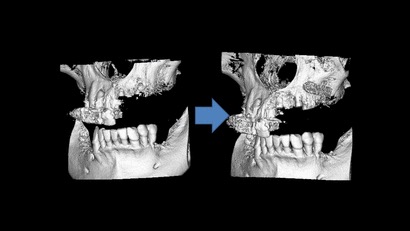

抜歯即時埋入や、サイナスリフト、GBRなど高度な治療も行っています。

インプラント1本埋入のケースでも事前にCTシミュレーションを行い、副鼻空との関係や、下顎臼歯部なら下顎管との距離や補綴する歯との位置関係を把握します。

全顎的にインプラント治療を行った症例

サイナスリフトにより上顎洞の横から

骨に穴を開け骨造成を行った症例